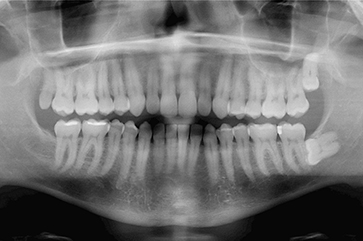

Tomamos una radiografía lateral de la cara y una radiografía panorámica de la boca con el fin de medir la posición y tamaño de los huesos faciales, dientes y labios.

Con la radiografía panorámica analizamos la salud de las piezas dentarias y tejidos en los que vamos a trabajar: dientes, encías y articulaciones con el fin de no alterar y mejorar y su salud y longevidad.